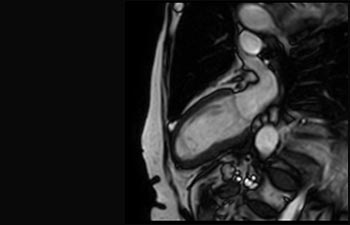

Infarto agudo de miocardio